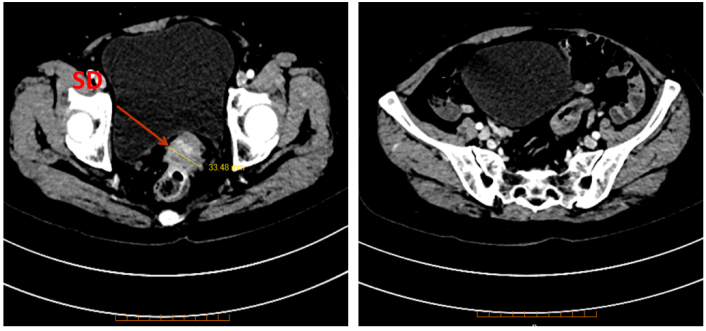

通过患者的影像学检查提示,直肠-子宫颈间病灶较前未见明显改变(表1)。疗效评价:疾病稳定(SD)。经多学科会诊(MDT)讨论评估,病灶可局部切除,建议先行同步放化疗后择期手术治疗。

表1. 腹部CT及盆腔MRI检查

腹部CT

2019年11月29日

图片

2020年1月12日

2020年2月18日

盆腔MRI

2020年2月17日

2020年4月4日

2020年4月28日

2020年4月30日